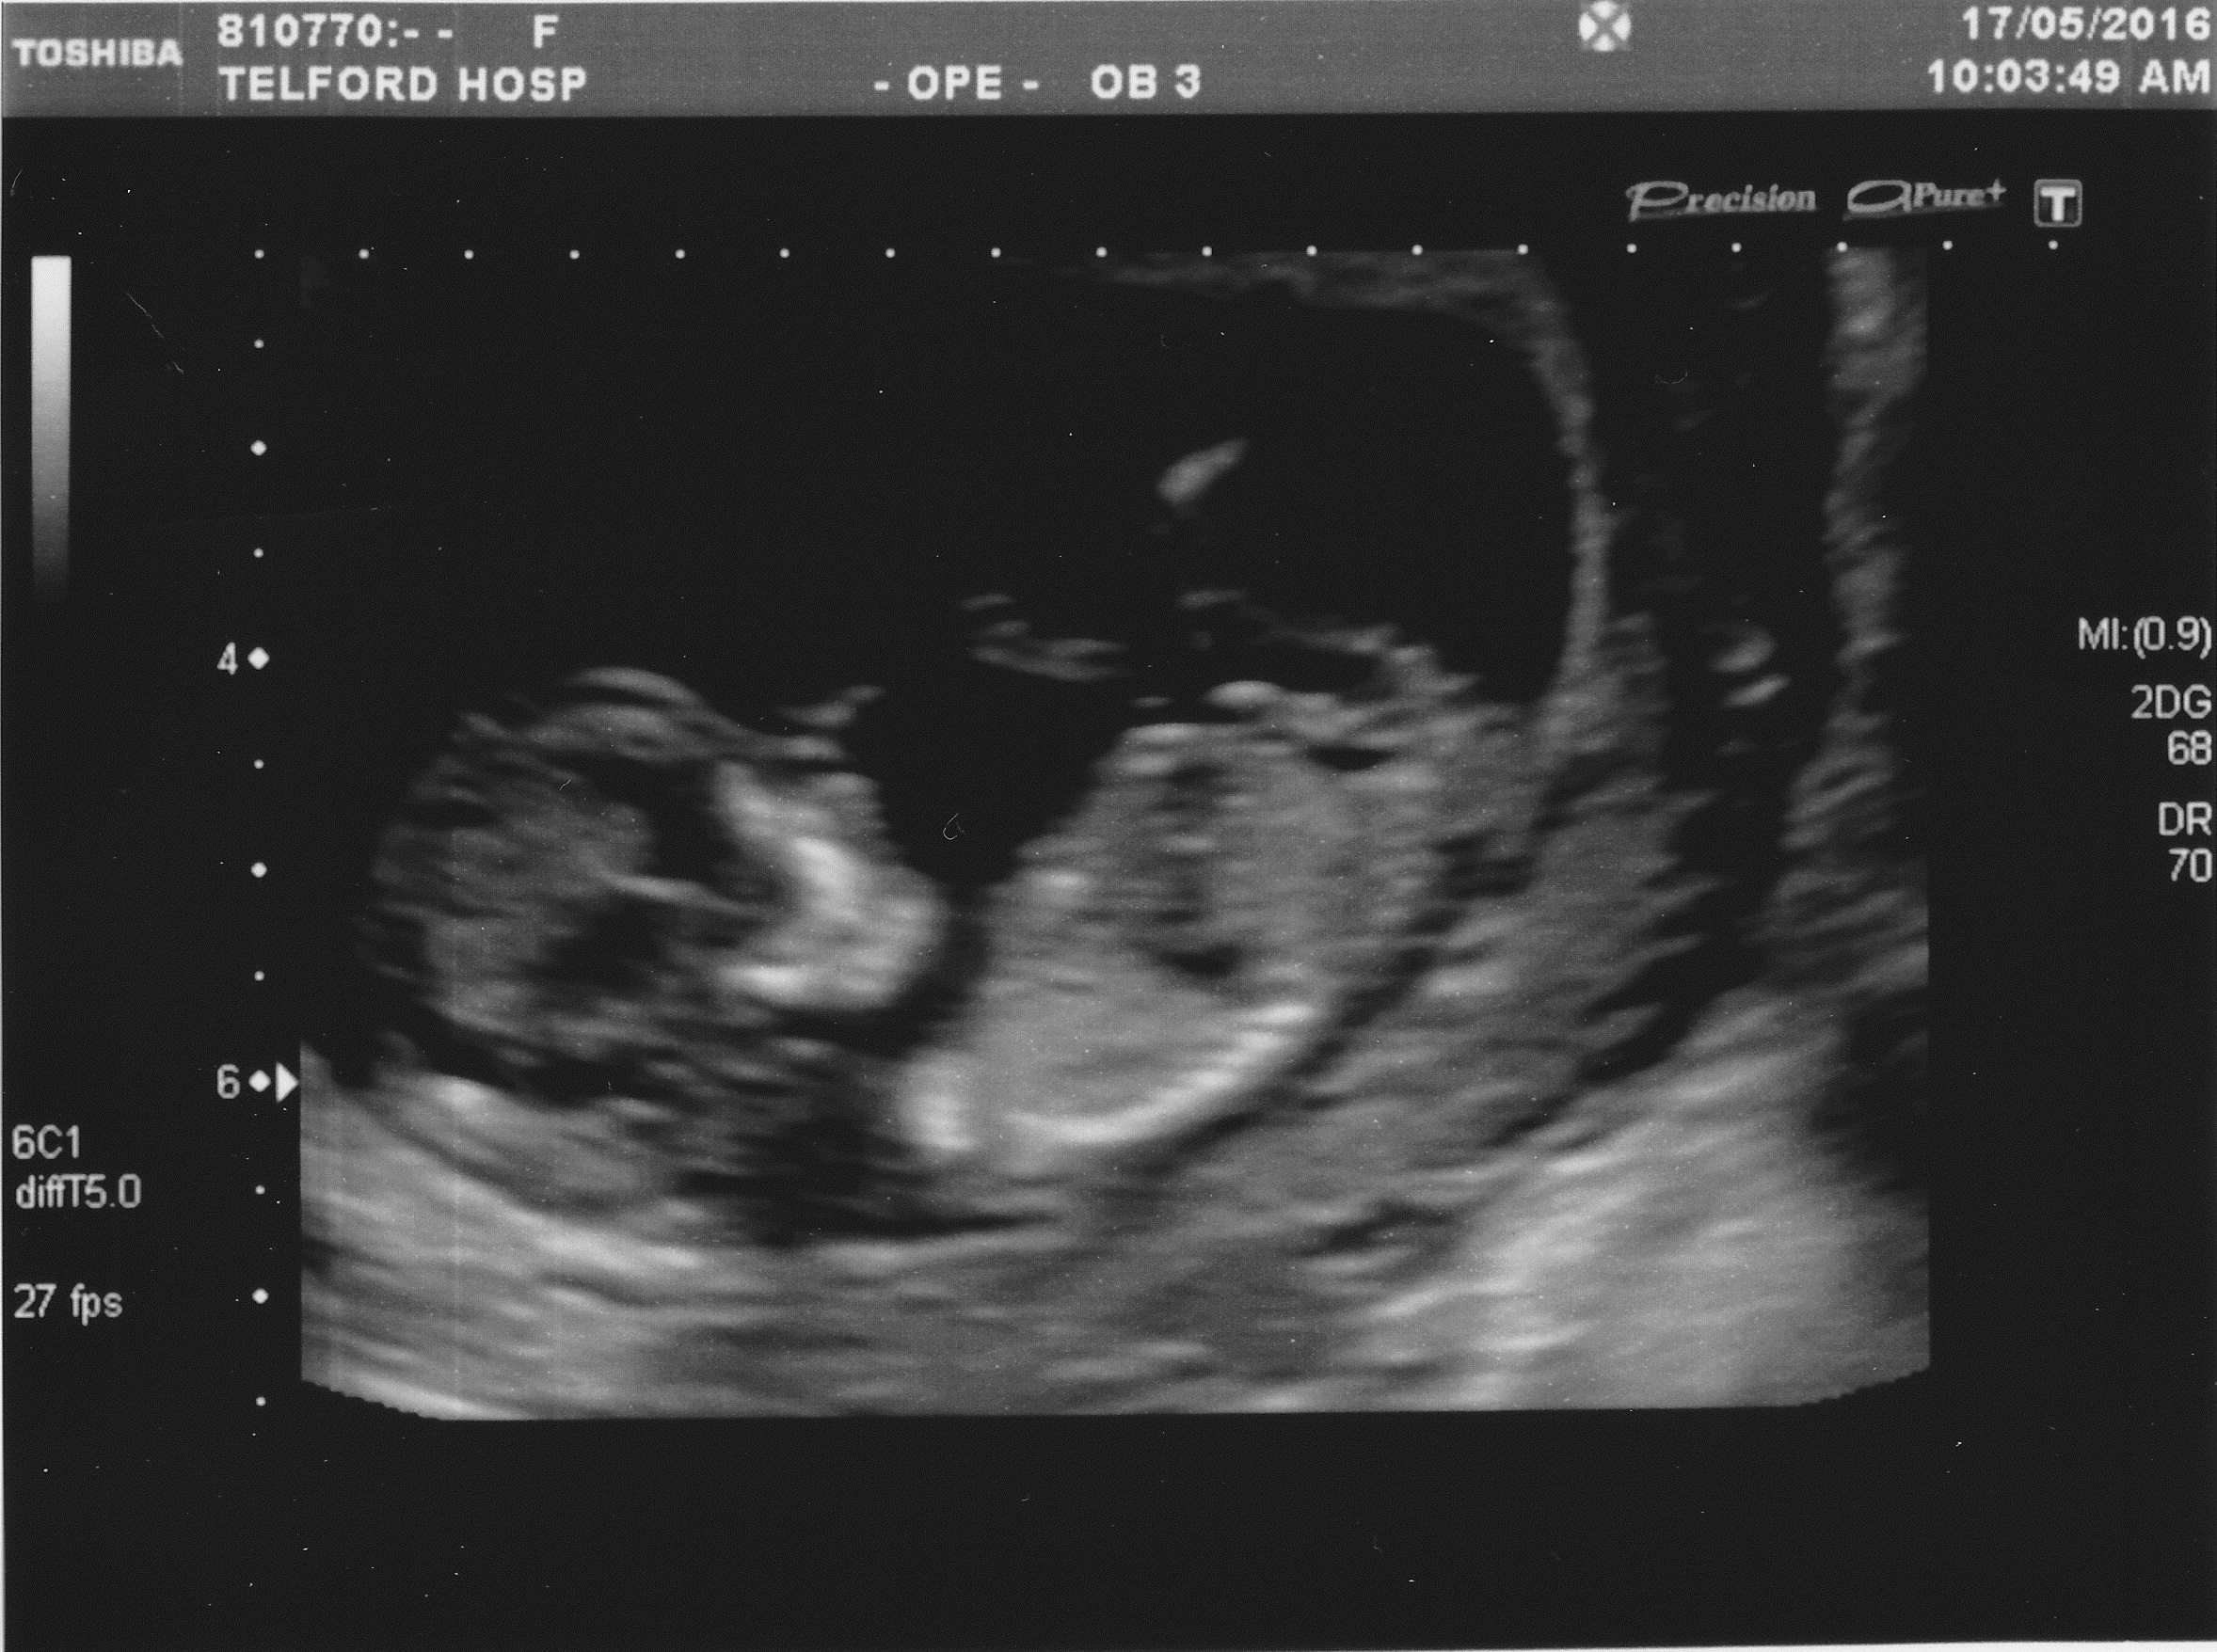

Attachment 32322

21 week scan above ^

Boy going by the last pic. I see a "turtle" between the legs. The other pics don't show anything.